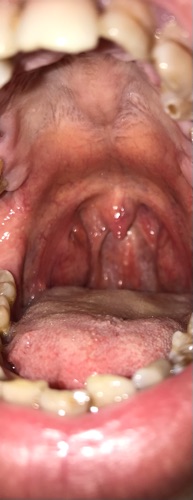

Em bị viêm họng kéo dài khô cổ có đờm , có phải viêm họng mãn tính không bác sĩ ? Em uống kháng sinh không khỏi? Xin bác sĩ tư vân

Có thể anh bị viêm họng do trào ngược anh ạ